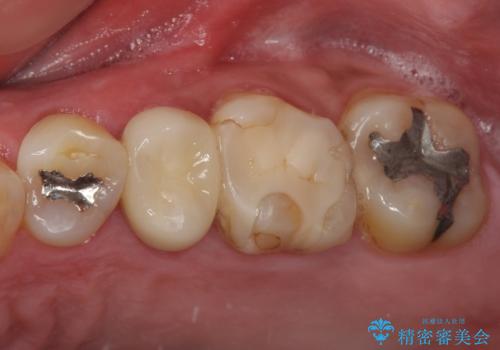

- 奥歯の詰め物が外れてしまったとのことで来院された患者様です。

根管治療の際に、咬み合う上顎の銀歯が内側に入り込んでいることも気になるとのことであったため、部分矯正を行い、その後上下を同時に補綴治療することとしました。

部分矯正を行うと咬み合わせが定まらないことがありますが、今回は矯正治療後に上下補綴治療を行ったため、安定した咬み合わせにて仕上げることができました。